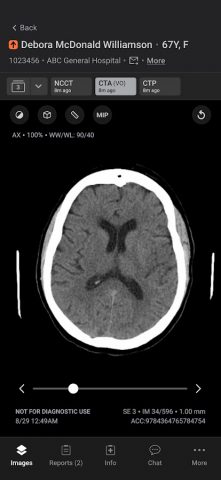

Мобильное приложение Aidoc оптимизирует коммуникацию, ускоряя принятие решений в критических ситуациях и повышая качество медицинской помощи. Приложение обеспечивает приоритезацию и оповещение на основе ИИ о широком спектре острых патологий, включая окклюзии крупных сосудов и легочную эмболию, — все это через защищенное мобильное приложение, соответствующее требованиям HIPAA.

Автоматически работающий ИИ Aidoc автоматически получает и анализирует все соответствующие исследования для выявления подозрительных результатов. После того, как исследование отмечено, Aidoc выделяет подозрительные результаты непосредственно в рабочем процессе медицинской визуализации. При остром состоянии изображения и соответствующие данные электронной медицинской карты (включая тенденции) передаются в мобильное приложение для своевременного вмешательства медицинской бригады. Врачи могут устанавливать свои предпочтения в мобильном приложении, включая индикацию вызова, указание места проведения исследования и конкретные рабочие процессы. Aidoc помогает сократить время от сканирования до постановки диагноза, повышая эффективность, сокращая время до начала лечения и улучшая качество медицинской помощи.